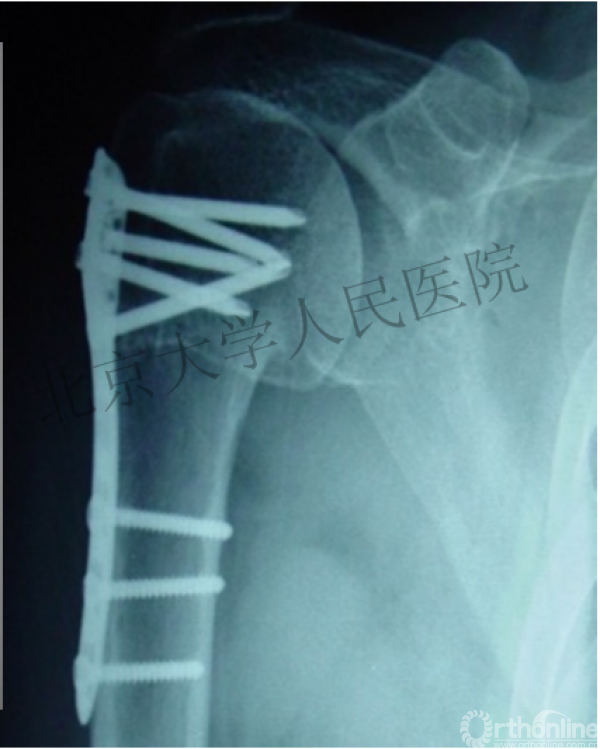

内侧皮质粉碎,低位外科颈骨折,肱骨头-干角维持困难。

术后复位丢失,肱骨头内翻畸形。

能否该偏心固定(钢板)为髓内固定,增加力臂?

早知今日,何必当初?

此时对比髓内钉是不是有很大优势?